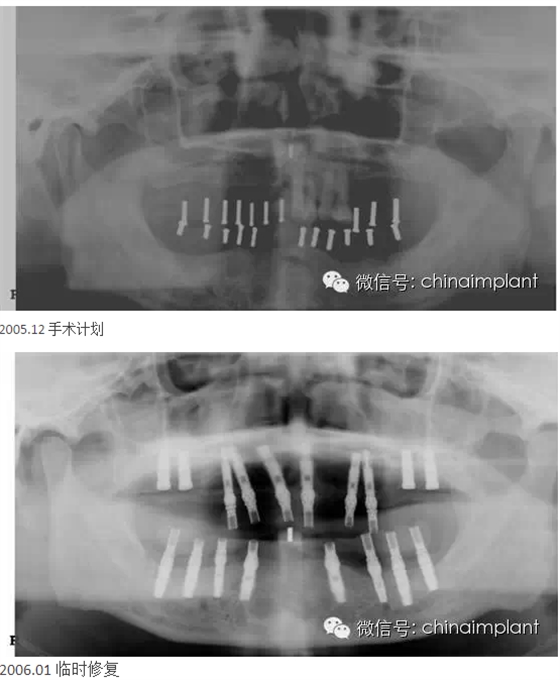

本案例已經(jīng)將近10年了(2005年12月),但是修復(fù)效果個(gè)人認(rèn)為很不錯(cuò),所以拿出來和大家分享。

從修復(fù)全景片上看到牙齒排列非常好